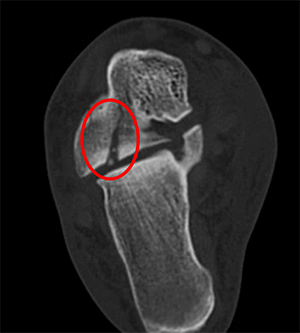

CT scan demonstrating the same fracture. Note the small fragments in the joint and the displacement between the joint surface